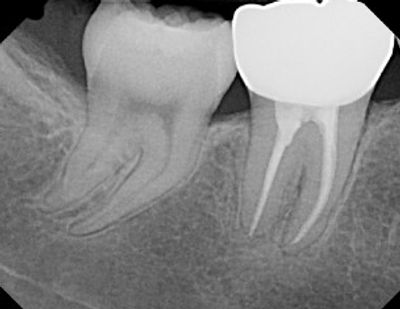

Root canal Treatment in wylie tx involves the removal of the diseased pulp along with the tooth nerve to relieve from pain and discomfort. The pulp chamber and the root canal of the tooth are cleaned, irrigated with medications and sealed with Gutta percha filling material. A dental crown is placed after finishing the root canal treatment to protect and strengthen the tooth. After the root canal treatment tooth is brittle due to lack of blood supply and nerve supply. slowly it gets fracture lines due to the forces from chewing and biting the hard stuff. To protect from breaking down Crown is needed to compensate the chewing forces.

After the crown restoration done, the tooth continues to function like a normal tooth.